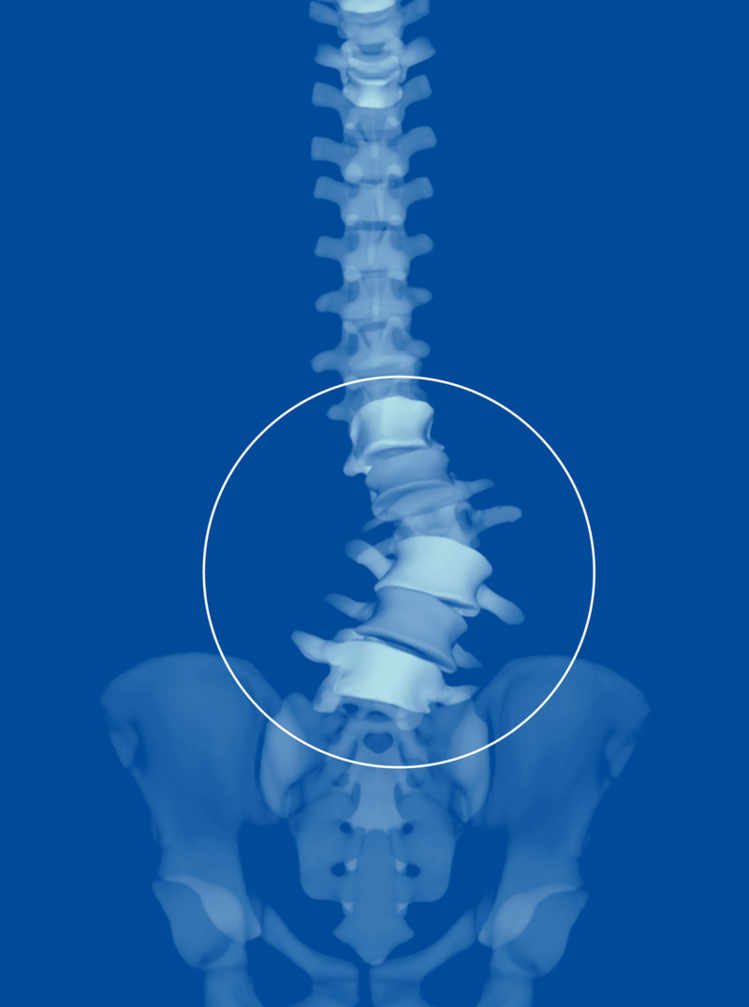

Les médecins se rendent compte que les maux de dos doivent être évalués de manière globale, qu'ils sont le résultat d'une interaction subtile entre la posture de la personne, sa musculature et des caractéristiques anatomiques qui lui sont propres. «Il existe un cône d'économie en position debout, relate le chirurgien, un ensemble de postures possibles où la musculature est sollicitée au minimum.» Quand on s'en écarte, celle-ci doit travailler davantage, ce qui augmente le risque de maux de dos.

On a désormais identifié des paramètres normaux, poursuit le chirurgien, des angles (de cambrure par exemple) ou des mesures (l'emplacement du centre de gravité) qui permettent de prédire si une personne risque davantage de connaître des maux de dos. Telle patiente, par exemple, a un sacrum presque à l'horizontale, illustre le spécialiste: c'est très rare et cela cause naturellement une cambrure exagérée qui explique ses maux de dos.

Ces valeurs, l'EOS les calcule aisément et les fournit rapidement. Une fois munis de ces données, les spécialistes comprennent mieux l'origine des maux de dos. Ces mesures sont également précieuses pour déterminer où opérer pour être le plus efficace, de même que pour évaluer comment la colonne s'est repositionnée après une opération.